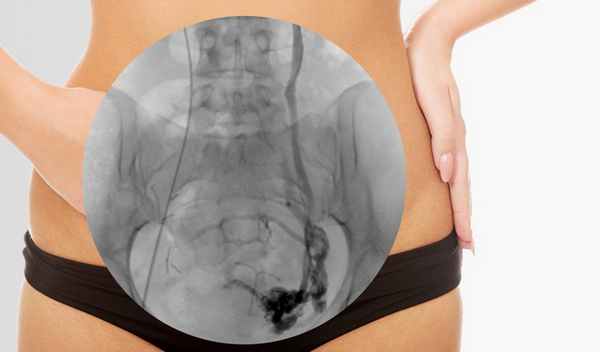

Флебография с контрастом

Контрастная флебография (венография, восходящая контрастная флебография или контрастная венография) — это рентгенологическое исследование глубоких или поверхностных вен с использованием контрастного вещества, которое обеспечивает изображение кровеносного сосуда. Флебография определяет проходимость глубоких вен, наличие тромбов, функцию клапанов и позволяет в целом оценить состояние глубоких вен.

Как проходит диагностика

Во время процедуры пациент лежит на специальном рентгеновском столе. Область, в которую будет вставлен катетер очищается (обычно это вена на руке, чтобы во время процедуры можно вводить любые необходимые лекарства). Иногда вводится местная анестезия.

Через катетер доставляется раствор контраста. Инъекция красителя вызывает ощущение тепла, которое может распространяться по телу. Контраст также может вызвать легкую тошноту. Около 18% пациентов испытывают дискомфорт от контрастного раствора. Чтобы заполнить глубокую венозную систему красителем, плотную ленту (или жгут) иногда накладывают вокруг лодыжки, или же конечности могут быть наклонены. Пациенту предлагается держать ногу неподвижно. Врач наблюдает за движением раствора через вену с помощью флюороскопа. В то же время делается серия снимков.